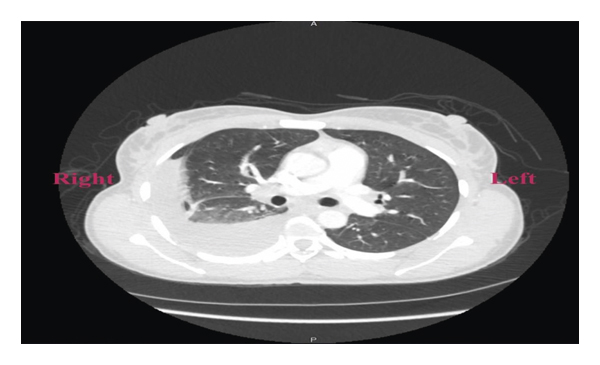

A 38-year-old Liberian female with a 12-week gestation presented to the emergency department with a 3-week history of low-grade subjective fever, night sweats, unintentional weight loss, gradually worsening abdominal pain, and intermittent spotting. Vital signs were stable on presentation, physical exam noticeable for gravida abdomen, otherwise unremarkable. Laboratory examination revealed beta hCG 118471, which was otherwise unremarkable. Pelvic ultrasound confirmed a 12-week viable intrauterine pregnancy. The patient was admitted to the hospital for close monitoring. Hospital course was complicated by massive pleural effusion, low-grade fever, progressive worsening abdominal pain, and spontaneous abortion. Non-contrast-enhanced computed tomography of the chest (Figure 1) revealed large right-sided pleural effusion, and contrast-enhanced computed tomography of the abdomen and pelvis (Figure 2) revealed bilateral hilar adenopathy, ascites, thickening and enhancement of the peritoneum, and mottled nodular-appearing soft tissue consistent with omental caking suspicious for peritoneal carcinomatosis. She underwent extensive workup including surgical and oncologist consultations for possible exploratory laparotomy and discussion of treatment options for presumed ovarian neoplasm. Blood work revealed elevated carbohydrate antigen (CA) 125 and positive QuantiFERON-TB Gold, but adenosine deaminase, CA 19, alpha-fetoprotein, and inhibin B were within normal limits. Diagnostic laparoscopy with biopsy revealed significant pelvis ascites and diffuse miliary lesions throughout the peritoneum. She underwent dilatation and curettage; histopathologic examination showed chronic granulomatous inflammation with no evidence of neoplasm. Special stains on tissue sections and ascitic fluid stain revealed rare acid-fast bacilli, suggestive of mycobacterial granulomatous peritonitis. Additional questioning indicated a history of positive PPD skin test a year prior without follow-up treatment. The patient was placed on four-drug anti-tuberculous therapy and had a complete recovery.